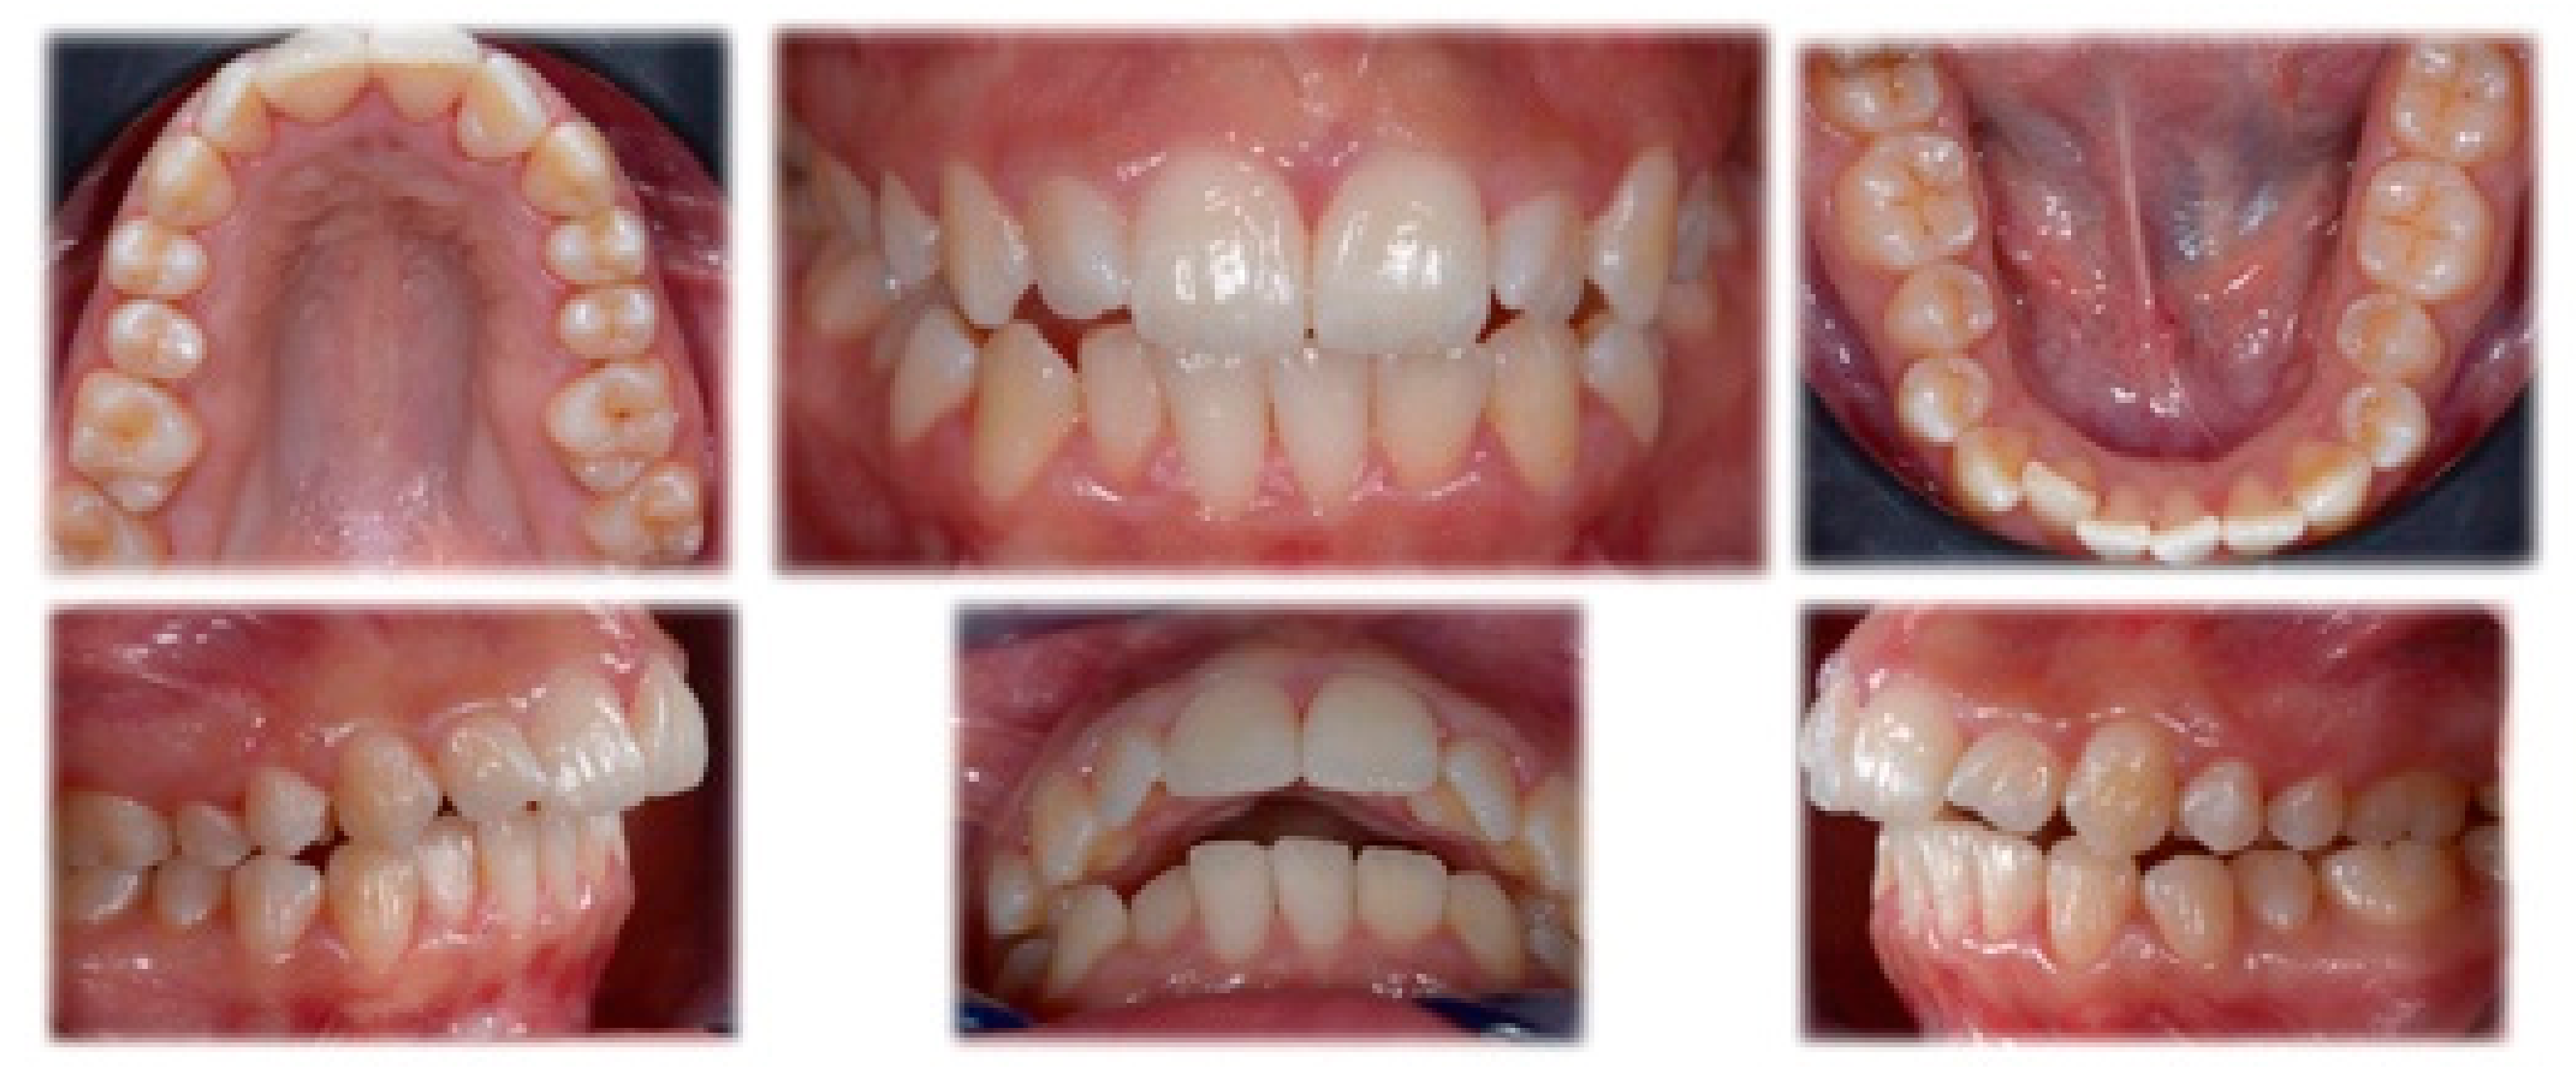

2.1. Diagnosis and Treatment Plan

2.2. Treatment Progress